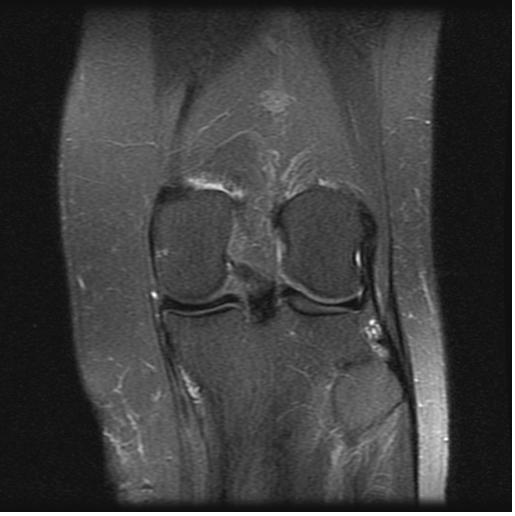

Click on images to enlarge.

My computer tech (who also has a certification in x-ray/mri technology) helped me to upload these two MRI images. He said he could also see what Dr. Main was talking about in that the white markings showing up on a T2 image is fluid accumulation above/around the head of the fibula. My only other diagnostic tool was a repeated Thermography scan on 5-7-13 that reiterated that my hyperthermia at the left popliteal fossa remained and was unchanged from previous scan on 12-6-11 and findings were consistent with underlying joint dysfunction.

Quoting from my office chart note the pertinent findings with the bold type my emphasis: “Musculoskeletal examination demonstrates her to walk about the clinic with assistive devices. She has a Coban wrap involving her left lower extremity from the knee to the ankle. Once removed she does have mild swelling overlying the lateral aspect of the left proximal leg region just below the level of the lateral joint line. There is a trace amount of swelling involving the left ankle….She is tender to palpation overlying the anterior tib/fib ligament, the distal tib/fib syndesmosis, the ATFL and the CCFL….Dorsiflexion and external rotation stress test elicits minimal pain at the ankle but more pain along the mid syndesmotic region. Cotton squeeze test is negative distally but is positive proximally….Examination of the left proximal tib/fib articulation demonstrates evidence of marked increase mobility of the proximal fibula in relationship to the tibia. She is noted to have a posterior and inferior instability pattern. This instability becomes worse with the leg externally rotated and it tightens with the leg internally rotated….X-rays from an outside facility reviewed about the left knee including AP and lateral demonstrates no gross evidence of arthritis changes present. The overall articulation of the proximal tib/fib joint appears to be well aligned….X-rays obtained today of her left ankle in our facility, AP, mortis and lateral views demonstrates the syndesmosis and ankle mortis to be well aligned. There are no signs of fractures or avulsion injuries noted….Outside MRI of left knee is also reviewed, which demonstrates no gross evidence of collateral or cruciate liagment tear or laxity or involvement. The meniscus appears to be intact. Minimal arthritic changes are present. There is mild increased fluid accumulation and swelling around the proximal tib/fib articulation.”